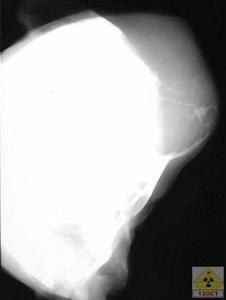

色素絨毛結節性滑膜炎1、本病的X線平片徵象包括關節腫脹和關節骨骼侵蝕破壞。軟組織腫脹呈結節狀,密度較高;PVNS骨侵蝕多自骨和軟骨交界處開始,故關節間隙一般保持正常。但關節積液量多時,關節間隙可增寬;繼發關節退變或關節軟骨遭受明顯侵蝕時,關節間隙可狹窄。

色素沉著絨毛結節性滑膜炎是涉及關節滑膜、關節囊和腱鞘的特發性增殖性損害,可為局灶性或瀰漫性,最常見於膝關節,髖關節次之。累及年輕患者的膝關節時整個滑膜受累,脛骨髁間嵴下受侵蝕。此時可見軟骨下肉芽腫,直徑3mm,類似脛骨巨細胞瘤。斷層位片可見股骨髁間窩骨皮質破壞。瀰漫型色素沉著絨毛結節性滑膜由於大量滑膜組織的增生,導致關節內壓力增高,絨毛易通過關節軟骨、骨與關節交界部或沿韌帶附著處侵入骨松質,骨組織侵犯多見於髖、踝關節,膝關節因關節囊腔寬大,骨組織不易受壓,骨破壞較為少見。